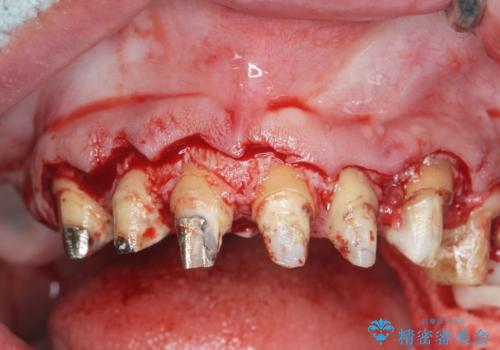

歯周組織検査を行うと歯ぐきからは容易に出血し、X線検査より歯とセラミッククラウンの適合が悪い(ピッタリと合っていない)状態が示唆され、歯ぐきの炎症を惹起している状態でした。

セラミッククラウンを除去し仮歯を装着し、歯周外科手術を行い歯ぐきの状態を改善したのち、適合の良いセラミッククラウンを再作製をする治療計画としました。